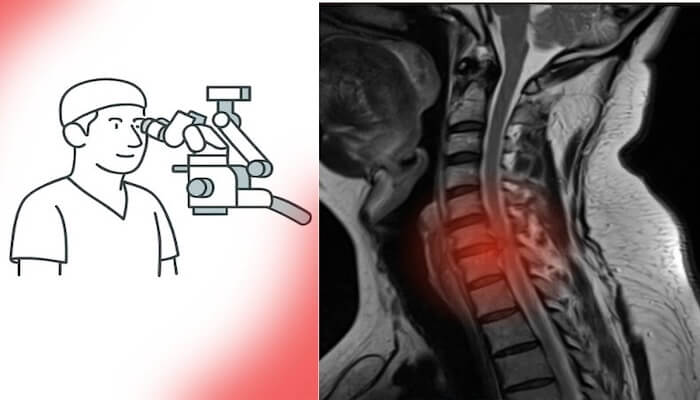

veya linki kopyala

Son yıllarda beyin ve omurga cerrahisinde hasta profili belirgin biçimde değişti. Artık ameliyat masasında sadece ileri yaşlı hastalar değil, genç erişkinler de yer alıyor. Özellikle bel fıtığı ameliyatı, boyun fıtığı ameliyatı ve hatta beyin tümörü ameliyatı geçiren hastaların yaş ortalaması giderek düşüyor. Peki bu değişimin sebepleri neler?

Günümüzde 25 yaşında bir hasta bel fıtığı ameliyatı, 30 yaşında boyun fıtığı ameliyatı, 35 yaşında ise beyin tümörü ameliyatı geçirebilmektedir. Bu durum, hem modern yaşamın omurga ve sinir sistemi üzerindeki erken yıpratıcı etkisini hem de tıbbın sunduğu güvenli ve etkili cerrahi çözümleri yansıtır.